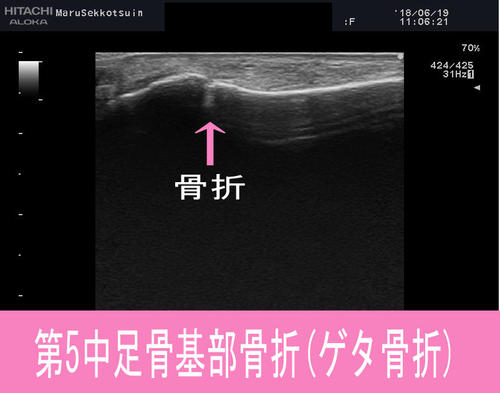

「第5中足骨基部骨折 (げた骨折) 」

いつものように、しっかりと問診・視診・触診後、エコー検査。

やはり"腫れ"の出現スピードから「第5中足骨基部骨折」

いわゆる「下駄骨折」といわれる骨折でございました。